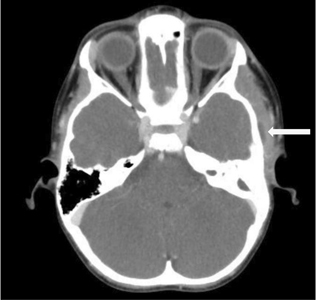

A Rare Complication of a Retrobulbar Hematoma Formation

Pompura fig 5 alternate text for this image

Following the Extraction of an Impacted Maxillary Wisdom Tooth The on-call team of Oral and Maxillofacial Surgery was notified to assess and treat a complication of retrobulbar hemorrhage and hematoma following the extraction of a left impacted maxillary wisdom tooth. This case is unusual as an ophthalmologic complication secondary to a dental extraction is very … Read more